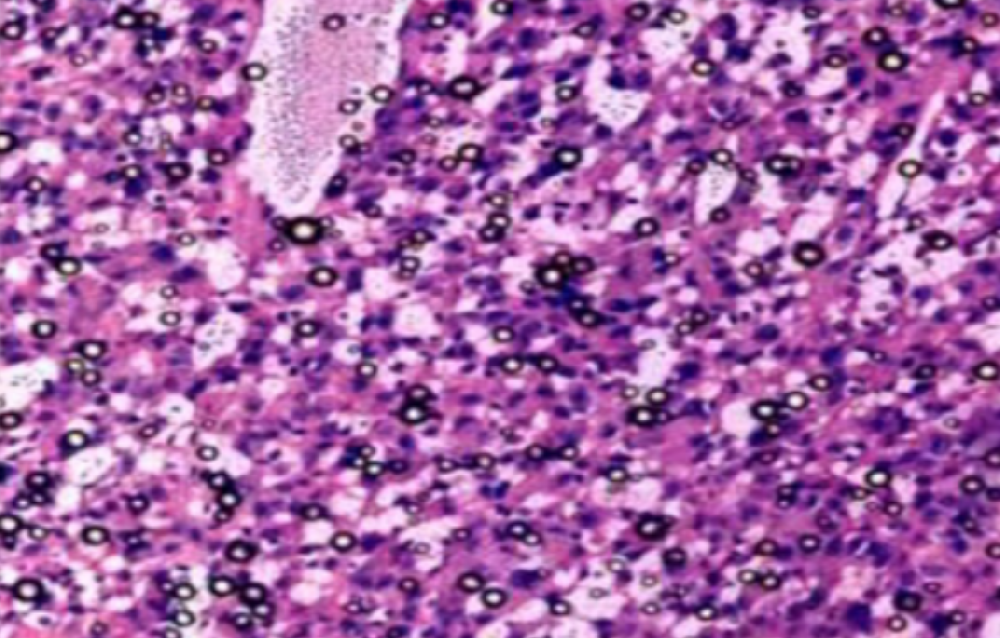

绍兴组织病理学实验